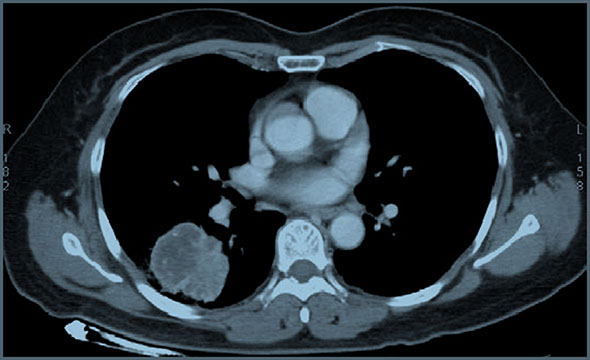

An abnormal chest x-ray shadow was detected in a 61-year-old woman in a regular check-up in August 2012. She was referred to our hospital due to a mass considered pulmonary carcinoma. The patient did not experienced any symptoms, such as cough, chest pain, fatigue, weight loss, but with carcinoembryonic antigen (CEA) 187.4 ng/ml. Bronchoscopy revealed chronic inflammation without carcinoma cell. She underwent preoperative chest and abdominal computed tomography, head magnetic resonance and bone imaging. It revealed a solitary mass measuring 4.8 cm in size without metastasis in other sites (Figure 1). In September, she underwent right lower lobectomy and mediastinal lymph node dissection. The histological diagnosis was poorly differentiated adenocarcinoma (pT2aN0M0, stage IB) (Figure 2A), with positive Thyroid Transcriptional Factor-1 (TTF-1) (Figure 2B) and Cytokeratin 7 (CK7). Mutational analysis revealed epidermal growth factor receptor (EGFR) wild type and anaplastic lymphoma kinase (ALK) negative. She was a non-smoker, but a Hepatitis B virus carrier for 21 years.

Figure 1: CT scan showing the mass in the right lower lung.